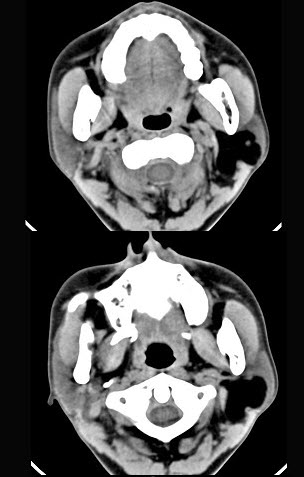

女性50岁,左侧面部肿胀,CT检查如图,应考虑为()。

A、左侧腮腺囊腺瘤

B、左侧腮腺囊肿

C、左侧腮腺脂肪瘤

D、左侧腮腺错构瘤

E、左侧腮腺炎

正确答案:

C